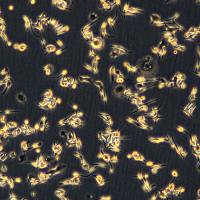

细胞名称:C1498细胞敲除mSdc1基因细胞系

细胞简称:C1498 KO-mSdc1 Cell Line

组织来源:淋巴母细胞

细胞形态:淋巴母细胞

生长特性:悬浮生长